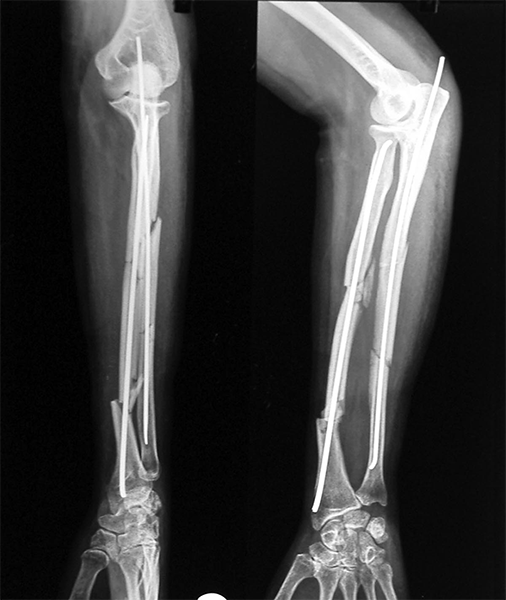

Case:6 Segmental Comminuted Fracture Radius

Patient, aged 75 years during morning walk tripped & had a fall following which he sustained injury to the left forearm. Closed reduction & interval fixation with Intra-medullary TEN nails was done in radius & ulna. Now he has full supination & pronation function of forearm.

Pre-Op

Post-Op

One and Half Months

3 Months Follow Up

4 Months Follow-Up